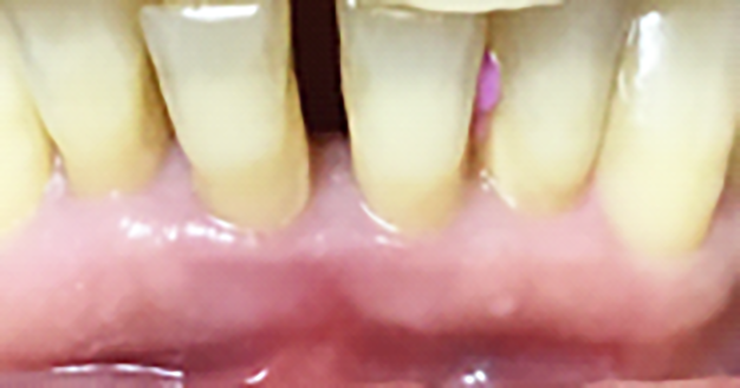

Previa anestesia locale si esegue lo scollamento di un lembo a spessore totale per consentire l’avulsione atraumatica degli elementi 3.1 e 4.1 (figure 1a-1b). Si revisionano le cavità alveolari e si posizionano osso bovino deproteinizzato e una membrana di collagene riassorbibile. Si sutura con filo 5/0, si posiziona un maryland bridge per garantire l’estetica in attesa dell’inserimento implantare e si esegue una radiografia di controllo (figure 2-4).

In seguito all’estrazione degli elementi 3.1 e 4.1 si osserva a una settimana di follow up la perfetta guarigione dei siti (figure 4-5). I successivi follow up mostrano come la rigenerativa abbia ristabilito gli adeguati volumi ossei e grazie all’analisi tridimensionale dei siti implantari è possibile pianificare correttamente il posizionamento degli impianti (figura 6).